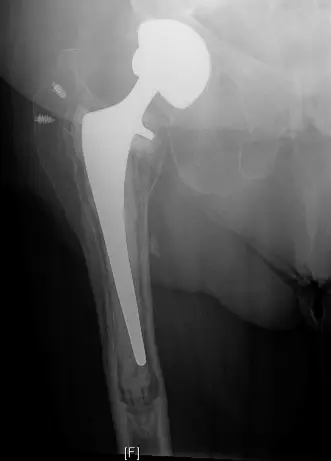

صورة توضيحية لـ كسور حول المفصل الصناعي: دليل شامل للمرضى مع الأستاذ الدكتور محمد هطيف في صنعاء